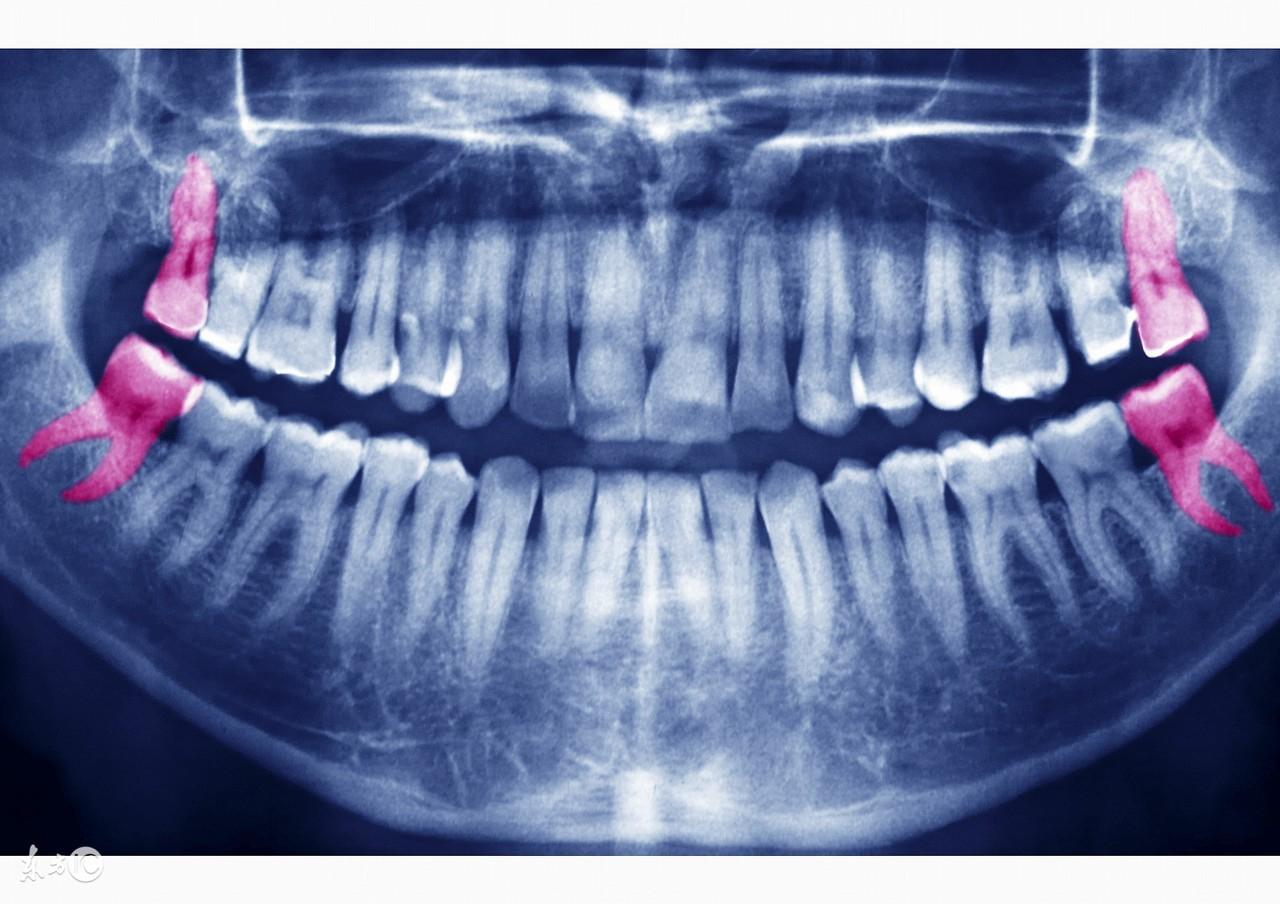

想瘦臉是廣大愛美人士的共同追求,我們經(jīng)常可以看到不少面容大變的明星說,自己臉變小只是因?yàn)榘瘟酥驱X而已。智齒作為遲長出的牙齒,還容易長歪引發(fā)疼痛,本來就讓人除之而后快,如果還能瘦臉豈不是一舉兩得?可真的有這種好事嗎?

要說拔智齒能瘦臉,這大多只是明星的一個(gè)說辭,要知道決定臉部大小的主要是骨骼、肌肉、脂肪。下頜牙齒對臉型的影響主要是支撐嘴唇(前牙)和臉頰(后牙),維持臉部高度,這跟牙齒是沒什么關(guān)系的。

為什么有人拔智齒以后臉會(huì)變?。窟@其實(shí)也并非真正的瘦臉而是因?yàn)槟[脹消除。由于智齒大多會(huì)錯(cuò)位導(dǎo)致發(fā)炎腫脹,當(dāng)拔掉智齒后,控制飲食配合恢復(fù),這也可能導(dǎo)致拔智齒的人變瘦,臉也隨之變瘦。

此外,智齒也并不是每個(gè)人都能拔,有血液病、先天性心臟病、肝損傷、高血壓、糖尿病等疾病的人,拔智齒易引發(fā)并發(fā)癥,因此不適合拔智齒。如果智齒生長良好,其實(shí)也沒有必要為了想要瘦臉而硬要把它們拔掉。